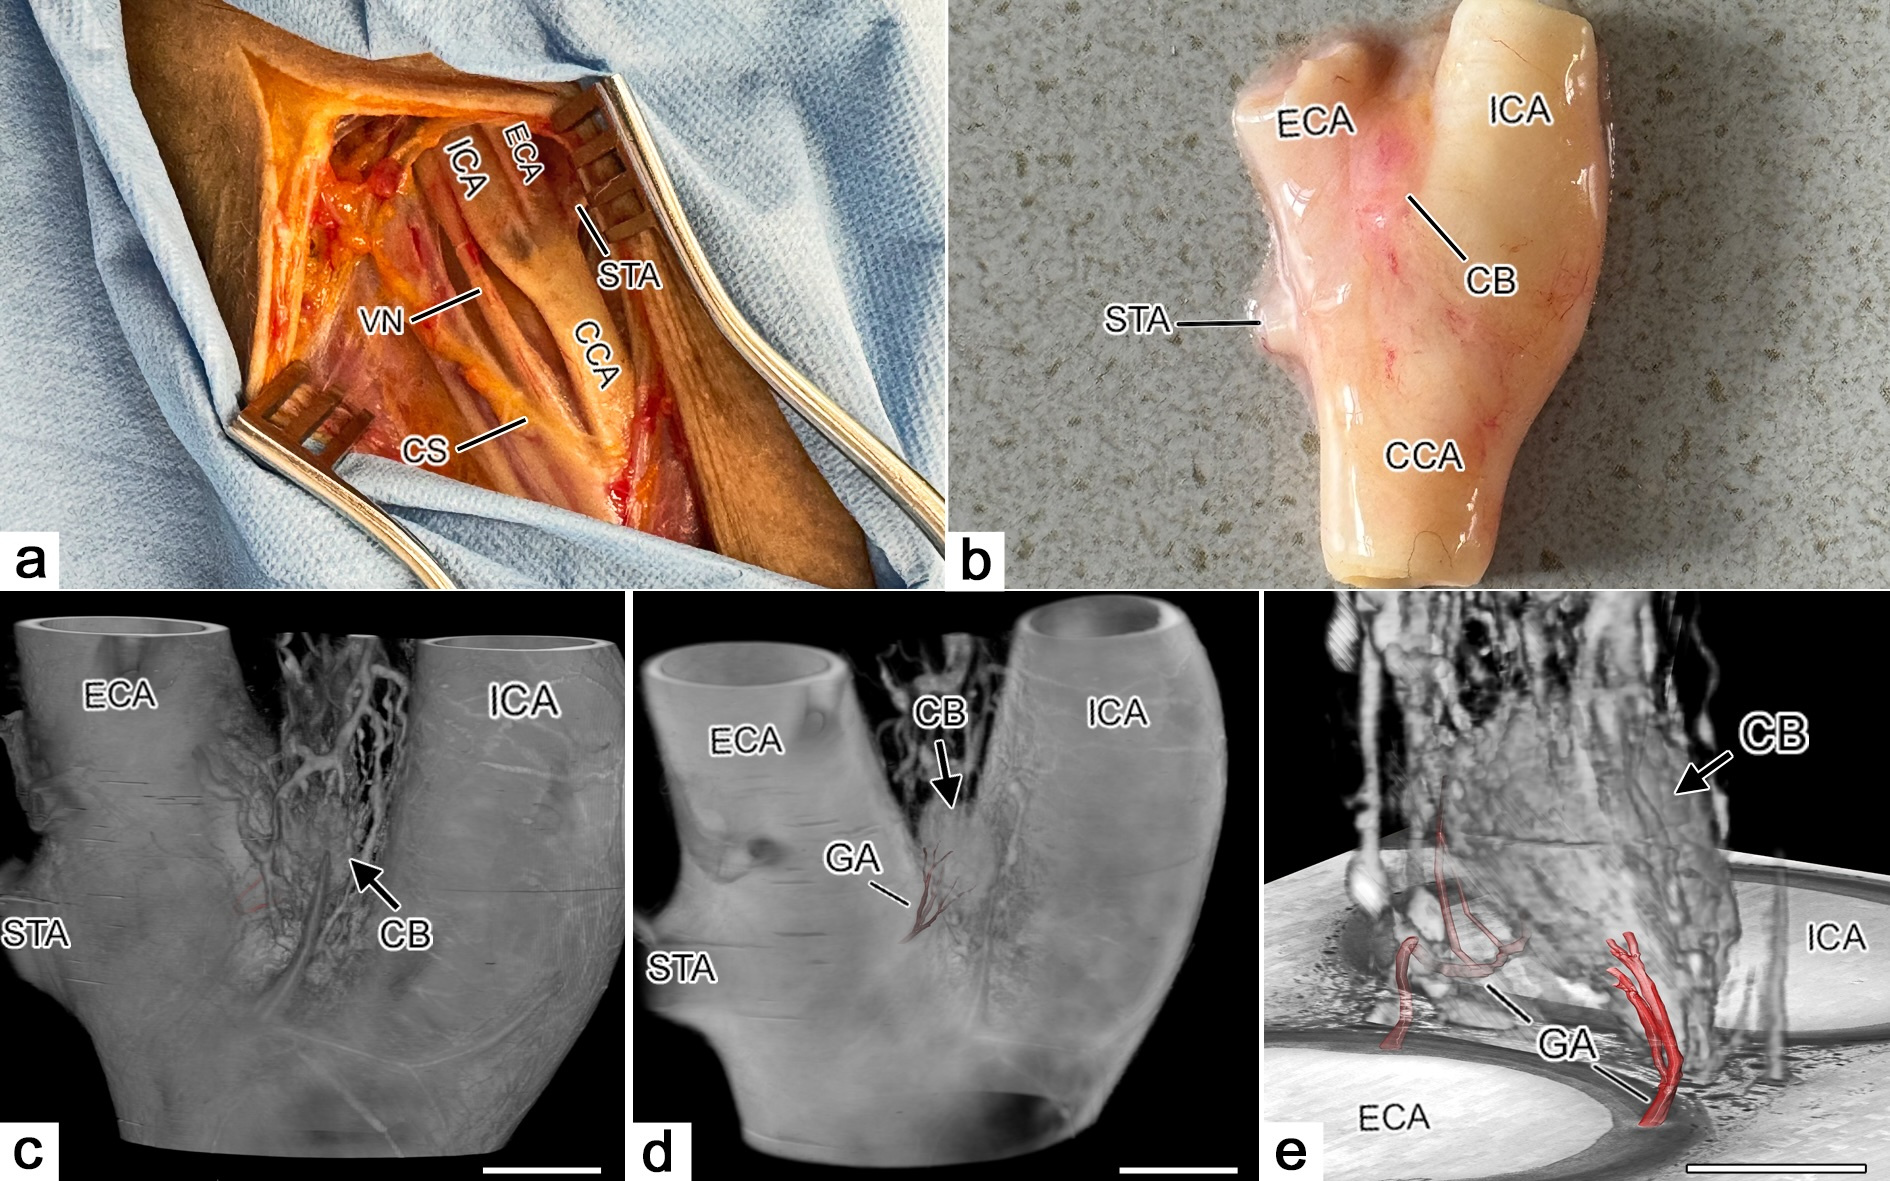

The carotid body (CB) is a highly vascularized chemosensory organ located near the bifurcation of the common carotid artery. Despite its clinical importance—in surgeries, tumor development, and cardiorespiratory regulation—there was a lack of detailed, large-scale 3D anatomical data on its arterial blood supply. The study aimed to fill this gap using high-resolution 3D imaging techniques to better understand the vascular architecture of the CB and its variability.

1. Location of the CB relative to the carotid bifurcation:

* 66.7% were posterior to the bifurcation

* 25.8% above it

* 7.5% anterior to it

2. Number of Glomic Arteries (GAs):

* Up to five arteries per CB

* In 25% of cases, only one GA was present

* In 54% of cases, two GAs were found

3. Origin of GAs:

* In 60% of cases, at least one GA originated from the external carotid artery (ECA)

* In 85% of cases with multiple GAs, at least one arose from the ECA